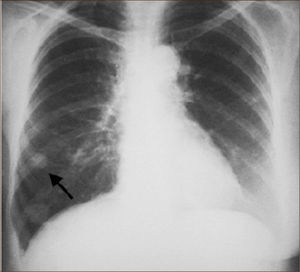

Un nódulo pulmonar corresponde por tanto a tumores Etapa I (T1a o T1b). Estas lesiones especialmente las menores de 2cms no son visibles a la Radiografía de Tórax siendo sólo pesquisables mediante TAC, especialmente cuando son subsólidas.

El diagnóstico por imágenes mediante TAC de Tórax, cumple por tanto un rol fundamental en la identificación y caracterización de los nódulos pulmonares. Los cánceres pulmonares iniciales pueden presentarse como nódulos de diferente densidad: sólidos, cavitados, en vidrio esmerilado (VE: definidas como una intensidad discretamente mayor a la del parénquima pulmonar a través de la cual la vasculatura pulmonar es visible) o lesiones mixtas con componente sólido y VE. Figuras 2 y 33. En etapas más avanzadas los CPNCP se presentan como nódulos de mayor tamaño o masas (>3cms), sin embargo también pueden presentarse como lesiones consolidadas mal definidas, especialmente algunos adenocarcinomas productores de mucina. Estas lesiones pueden ser indistinguibles de una neumonía, pero a diferencia de estas persisten en el tiempo pese al tratamiento antibiótico 27,28.

DETECCIÓN PRECOZLa gran mayoría de los CPNCP tiene una etapa pre-clínica prolongada, por lo que desde hace años se ha estudiado la posibilidad de utilizar estudios de imágenes para tamizaje. Estudios realizados en los años 60 mediante radiografía de tórax no demostró ser útil en disminuir la mortalidad por cáncer pulmonar58.

A partir de los años 90 se comenzó a realizar diferentes estudios utilizando el TAC de Tórax para le detección precoz de cáncer pulmonar. El Anti-Lung Cancer Association Project en Japón, permitió pesquisar 11.5% cánceres versus 3.4% con radiografía, el 71% de los tumores correspondían a etapas tempranas22. En Estados Unidos el Early Lung Cancer Action Project, pesquisó 2.7% de cánceres pulmonares, de los cuales 85% correspondía a etapa I23. Estudios iniciales en nuestro país con detección han demostrado cifras similares, se pesquisa entre un 39 a 71% de NP de los cuáles entre 1.5 a 2.7% corresponden a CP59–61.

Recientemente el National Lung Screening Trial permitió demostrar claramente que el tamizaje con TAC de Tórax de baja dosis es útil para la detección precoz de cáncer pulmonar. Este estudio multicéntrico incluyó a 53.454 individuos mayores de 55 años con gran carga tabáquica (más de 30 paquetes/año); obteniendo una reducción en la mortalidad por cáncer pulmonar de 20% en los individuos seguidos con TAC de Tórax en relación a los seguidos con Radiografía de Tórax15.